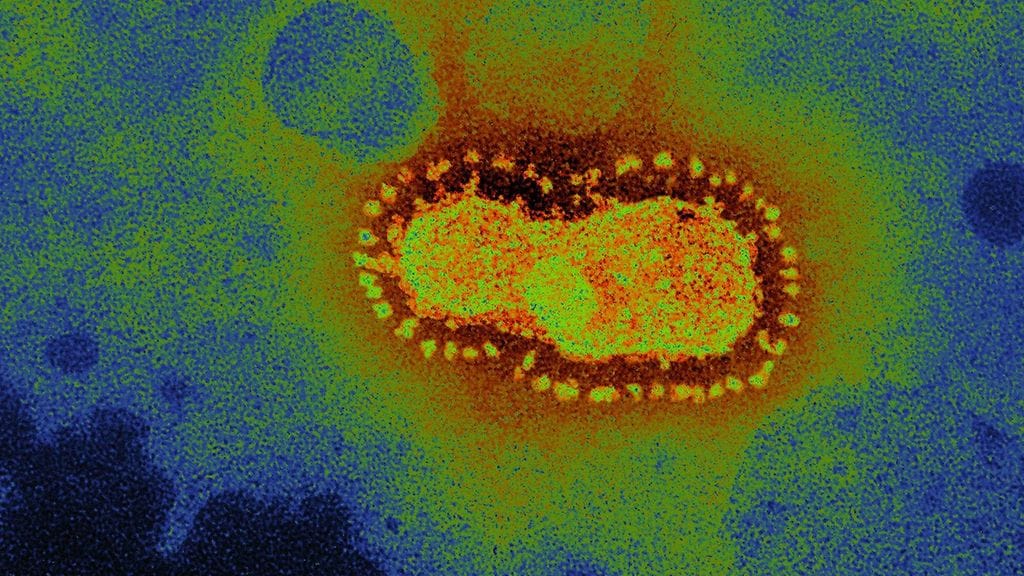

Terveysviranomaiset ovat julkaisseet tiedon ensimmäisestä Euroopassa tapahtuneesta uuden koronaviruksen tartunnasta ihmisestä toiseen.